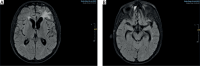

Cerebral vasculitis secondary to pneumococcal meningitis. Plasmapheresis as adjuvant therapy. Case report